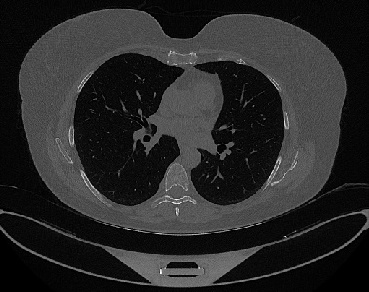

It should be mentioned that for explainability purposes [7, 8, 9], an anchor set was generated for the COV19-CT-DB database [5]. This included 11 anchors, each representing a respective 3-D CT scan obtained through an appropriate clustering procedure. Figure 2 shows a series of slices from a COVID-19 case, whereas Figure 3 shows a series of slices from a non COVID-19 case.